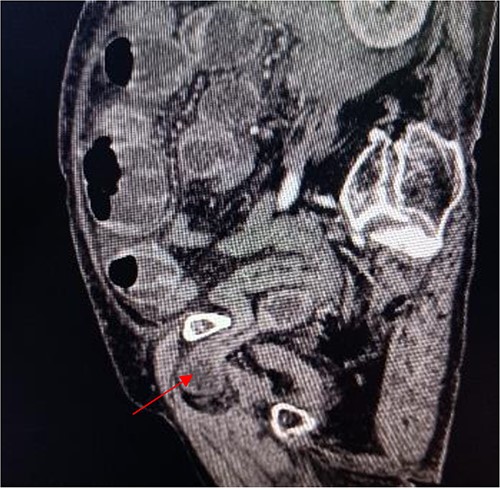

Coronal view shows right obturator hernia entering the intestinal canal (indicated by red arrow).

An 86-year-old female complained of constipation with abdominal pain, nausea, and vomiting for ˃2 weeks. The patient had defecated once, after conservative treatment with an enema in a local hospital, with less abdominal pain and no nausea or vomiting; hence, she was admitted to our hospital for further diagnosis and treatment. The patient’s body temperature was 36.8°C, pulse rate was 87 beats/min, respiration rate was 18 breaths/min, and blood pressure was 125/76 mmHg. The patient was conscious and had a thin appearance, and physical examination indicated that the abdomen was soft, and without tenderness and rebound pain. Routine blood examination showed that hemoglobin was 87 g/L and hematocrit was 28.3%. Abdominal computed tomography revealed the right lower abdominal small intestine protruding into the femoral triangle through the obturator; the upstream intestine was distended and expanded, and multiple fluid levels were observed in the intestinal lumen. Multiple lymph nodes were noticed in the abdomen and retroperitoneum; the large ones had a diameter of ~1 cm. Uneven thickening and enhancement of the local ascending colon were noted.